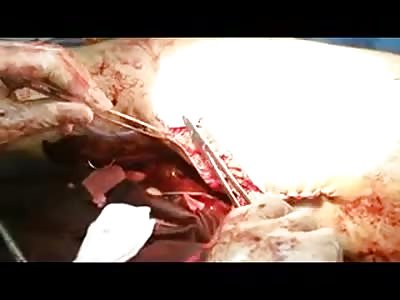

An “enormous” gossypiboma, which is a mass inside the body composed of retained surgical gauze or sponge surrounded by an inflammatory foreign body reaction.